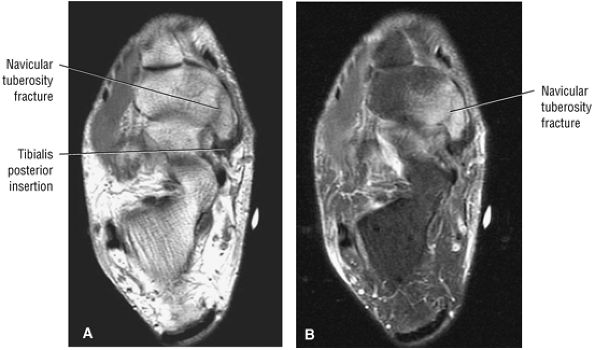

FIGURE 5.26 ● Coronal anatomy of the ankle and foot. (A) The calcaneofibular ligament (CFL) is identified by finding its origin at the inferior tip of the lateral malleolus. The posterior inferomedial course of the CFL is followed on three or four consecutive coronal images moving posteriorly through the ankle, to its insertion on the posterolateral calcaneus. Optimal evaluation of the CFL involves examining its full course on successive images in both the coronal and sagittal plane for tears, sprain, or scarring. (B) The medial cord of the plantar aponeurosis is normally slightly thicker than the lateral cord, and this mild asymmetry in thickness should not be misinterpreted as plantar aponeurosis scarring or plantar fasciitis. On successive coronal images, the course of the plantar aponeurosis should be followed back to its insertion on the inferior calcaneus and evaluated for the presence of thickening, decreased signal suggestive of scarring, increased signal indicative of plantar fasciitis, and tears. (C) Coronal images are optimal for viewing the lateral process of the talus, which is a frequent site of fractures that are occult on plain films. Fractures of the lateral process of the talus are most common in patients with snowboarding injuries. (D) The talar dome and tibial plafond are optimally visualized on coronal images. They are assessed for the presence of subchondral edema and cystic change with overlying chondral abnormalities. Close attention should be directed to the extreme anterior and posterior margins of the cartilage-bearing articular surfaces of the talar dome and tibial plafond to avoid overlooking osteochondral lesions at these locations. (E) The origin of the anterior talofibular ligament (ATFL) is found at the anterior distal tip of the lateral malleolus, and the ATFL is followed anteriorly on two or three successive coronal images to its insertion at the anterior lateral margin of the talus. (F) The deltoid ligament is optimally visualized in the coronal and axial planes. Tears of the deltoid manifest as loss of fiber striation or diffuse amorphous hyperintensity in the ligament on fluid-weighted sequences. Partial tears are more common than complete tears. (G) Focal fatty atrophy and denervation of the plantar flexor muscles of the foot (abductor digiti minimi, flexor digitorum brevis, and abductor hallucis) may indicate neuropathy involving the tibial nerve or its branches. (H) At the level of the anterior aspect of the talus and calcaneus, the peroneal tendons and flexor tendons turn from their cranial—caudal course to travel an anterior-to-posterior course along the plantar aspect of the foot. The distal portions of the tendons should be examined along the plantar aspect of the foot on successive coronal images for evidence of tendinosis and tears. (I) The base of the fifth metatarsal is a common location for fractures and is often visualized within the FOV on ankle MR exams. (J) At the level of the navicular, the flexor digitorum longus (FDL) and flexor hallucis longus (FHL) tendons run side by side, with the FDL medial to the FHL. Anterior to this level on successive coronal images, the two tendons cross, with the FHL medial to the FDL as the FHL courses to its insertion on the great toe. (K) Stress fractures of the navicular are commonly vertical in the midline of the navicular, an appearance that is well characterized on coronal images. (L) Contusions, stress-related edema, fractures, and degenerative arthritis of the midfoot bones and joints are common causes of midfoot pain and are often optimally identified on fluid-sensitive sequences.